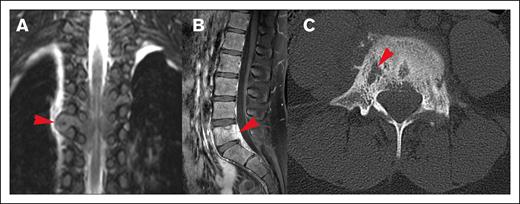

Different origins of CNS HL lesions. (A) Tumor originating from bone (vertebral body of T12, L1, and L2). (B) Unclear tumor origin but very likely bone, with circumferential involvement and an associated soft tissue component. (C) Paravertebral tumor mass of the upper thoracic spine infiltrating through the right neuroforamen, demonstrated by the red arrow, likely originating from soft tissue.

Most lesions (92.7%) extended through the neural foramina of either the vertebrae or sacral bone; 2 lesions did not extend through the neural foramina, and 2 lesions could not be evaluated (Figure 4). Thirty-one lesions entered the spinal canal. Of these, 54.8% caused displacement of the spinal cord, 25.8% were adjacent to the spinal cord but did not cause displacement, and 19.4% did not contact the spinal cord (Figure 5). None of the lesions infiltrated into the spinal cord itself. Spinal cord edema was evaluated for patients who had MRI available (17 of 31 lesions). Among these evaluable lesions, only 12.9% had evidence of spinal cord edema.